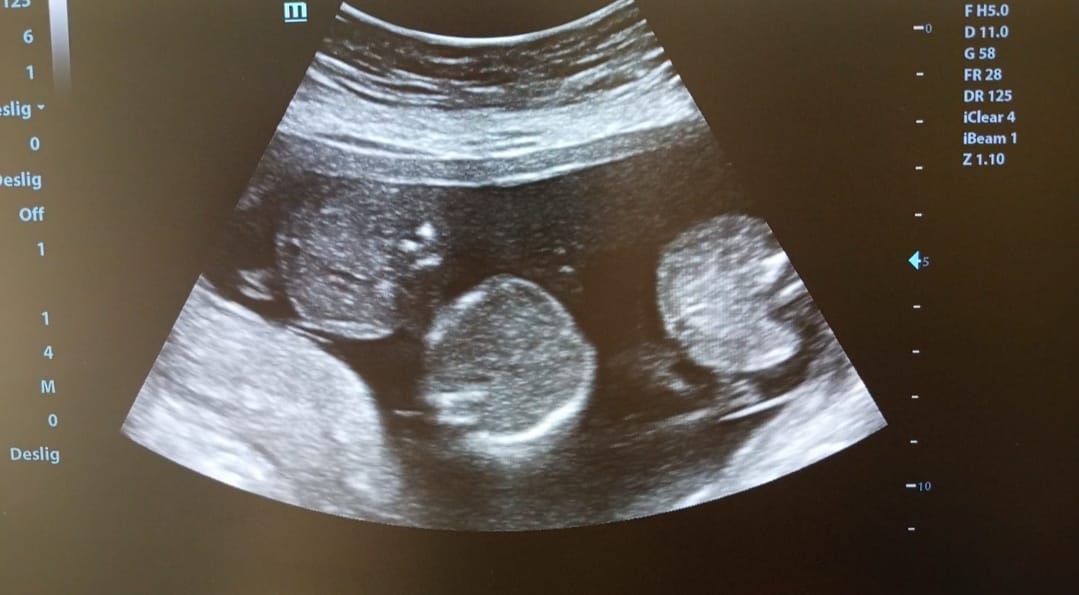

“Eu fui fazer o ultrassom sozinha. Deitei lá, o médico começou a examinar e simplesmente olhou para mim e falou: ‘São três bebês, são três, gêmeos’. Eu levei um susto, levantei e falei: ‘Como assim?’”, relembra.

Segundo Tatiane, o médico confirmou que se tratava de trigêmeos naturais. Sem ter realizado qualquer tratamento de fertilidade, ela recebeu a notícia de que a gestação era considerada extremamente rara. “Ele perguntou minha idade, eu falei 39 anos. Aí ele disse que realmente eram trigêmeos.”

“Ele disse que não teria como ser os três em uma placenta só, que era muito raro. Quando repetimos o exame, foi confirmado: é uma gravidez rara, três bebês em uma única placenta, cada um no seu saco gestacional e com seu próprio cordão”, conta.

Atualmente com 23 semanas de gestação, Tatiane afirma que os três bebês estão bem e seguem sendo monitorados constantemente. A previsão inicial de parto é 26 de junho, mas, por se tratar de trigêmeos, os médicos já consideram a possibilidade de antecipação.